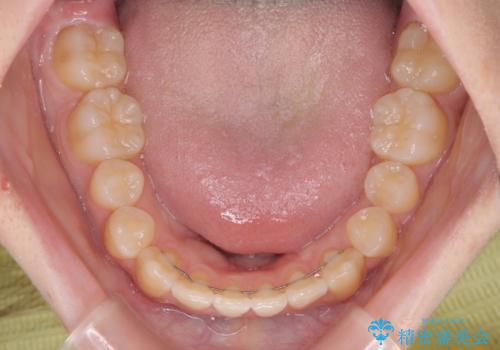

前歯のクロスバイト メタル装置での矯正治療

- 前歯のクロスバイトを気にして来院された患者様です。

当初は1年半程度の治療期間を想定していましたが、上下の正中を合わせていく過程で奥歯の咬みにくさが続いてしまい、2年以上の治療期間を要することとなりました。